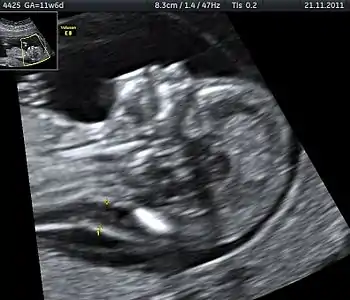

Tetrasomy 9p is a rare condition in which people have a small extra chromosome that contains two copies of part of chromosome 9, in addition to having two normal chromosome 9's as well. This condition may be diagnosed by analyzing a person's blood sample since 9p is found in high concentrations in the blood. Ultrasound is another tool that may be utilized to identify tetrasomy 9p in infants prior to birth. Prenatal ultrasound may reveal several common characteristics including: growth restriction, ventriculomegaly, cleft lip or palate, and renal anomalies.[30]